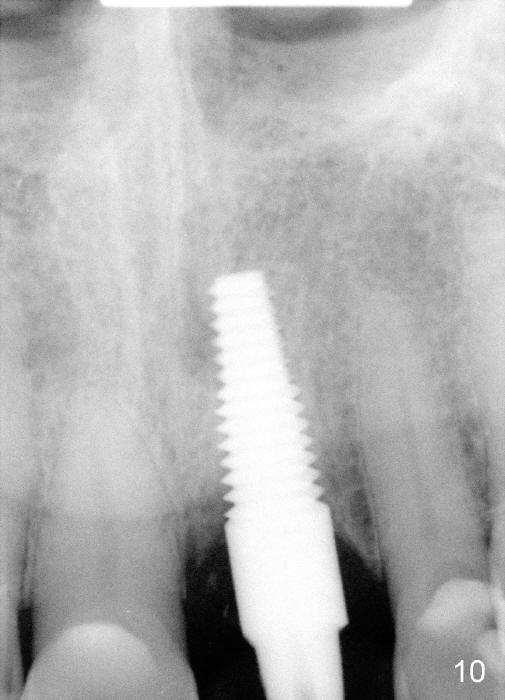

Postop tenderness lasts for two days. The palatal swelling is unnoticeable 7 days postop (Fig.9 *, as compared to A in Fig.8). The bone remains stable around the implant (Fig.10), while the gingiva healthy around the immediate provisional (Fig.11) 5 months postop. Due to insurance limit, the permanent restoration is delayed (16 months postop, Fig.12). The patient is satisfied with the function and appearance 3 years 8 months postop (21 months post cementation, Fig.13,14). PA is taken 4 years 1 month postop (2.5 years post cementation, Fig.15). The lamina dura forms from the most coronal threads (Fig.16). Although there is no bone loss around the implant (Fig.17), metal starts to show 5 years 2 months postop (Fig.18 ^), probably related to the buccal placement, too large the implant for the site or buccal plate atrophy (Fig.19).